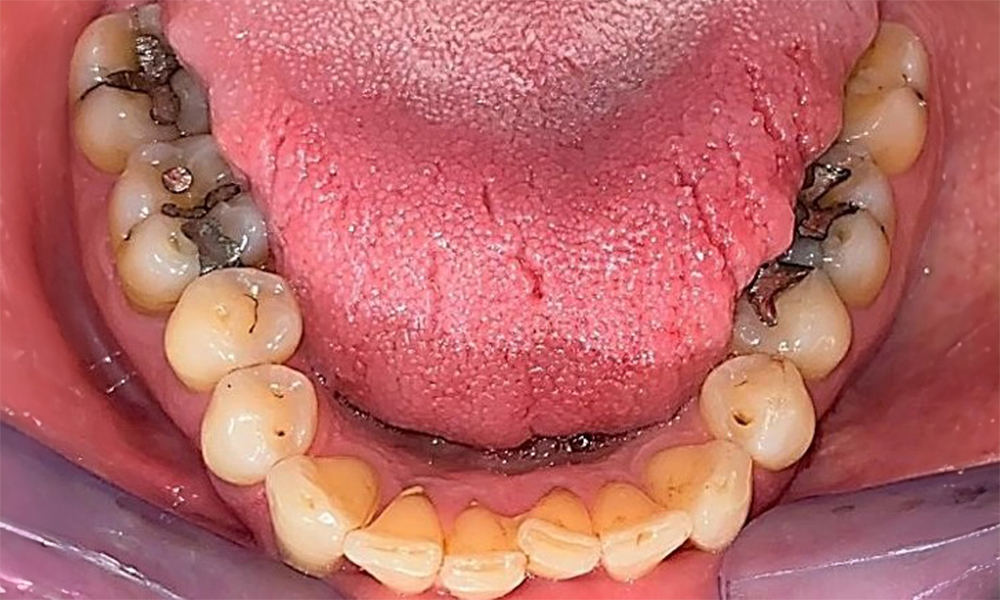

Зъбни резултати

Пациентът има пълно съзъбие с 28 зъба, което включва амалгамни и композитни пломби в областта на моларите и премоларите. На зъб 14 има видима клинична маргинална празнина. Зъб 27 има адекватна златна инкрустация. Налице са и генерализирани атриции и абразии. (фиг. 2, фиг. 3, фиг. 4, фиг. 5, фиг. 6)

Пародонтални резултати

Пациентът е с пародонтит II стадий, степен В (5). Клиничните дълбочини на сондиране от 1 до 3 mm са във физиологичния диапазон. Локализирани дълбочини на сондиране от 5 mm са наблюдавани медиопалатинално на 17 и 27. Налице са генерализирани рецесии от 1 до 3 mm с частична загуба на интердентални папили (фиг. 2, фиг. 3, фиг. 4)